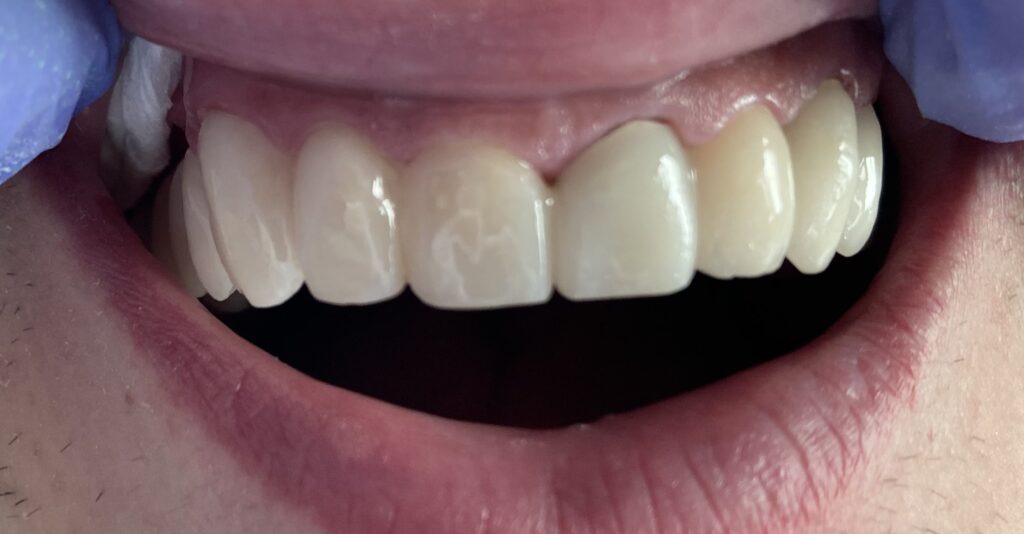

Każdy uśmiech ma swoją historię – my pomagamy ją opowiedzieć na nowo. Dzięki indywidualnie dobranym planom leczenia przywracamy pacjentom nie tylko piękny wygląd zębów, ale również komfort i funkcjonalność w codziennym życiu. Poniżej przedstawiamy wybrane przypadki metamorfoz, które pokazują, jak zaawansowana protetyka, nowoczesne techniki odbudowy oraz precyzyjne leczenie endodontyczne potrafią całkowicie odmienić uśmiech.